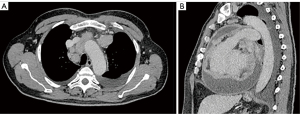

The pulmonary angiography revealed a right lobar/segmental PE (Figure 1) and a significant pericardial effusion (Figure 2) measuring 40 mm with a density of 15 HU. The patient was then admitted to the cardiology department for additional diagnostic evaluation. MSCT of the chest indicated enlarged paratracheal and subcarinal lymph nodes (Figure 3A,3B), while the MSCT of the abdomen showed no abnormalities. A transapical approach was utilized for the pericardiocentesis, during which 2.5 liters of hemorrhagic fluid were extracted and sent for cytological, microbiological, and biochemical examination. The subsequent results confirmed the type of exudative effusion, and the cytological examination indicated that there was intense and atypical growth of mesothelial cells. Thoracocentesis was subsequently performed and the analysis that followed corroborated the earlier findings. Due to suspicion of a systemic autoimmune disease or antiphospholipid syndrome, which could explain multisystem serositis (pleural and pericardial involvement), elevated inflammatory markers, thromboembolic event (PE), lymphadenopathy and constitutional symptoms, immunological tests were indicated.